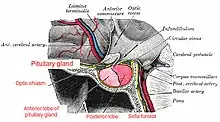

| Anatomy of normal pituitary gland and surrounding structures | |

Sheehan's syndrome, also known as postpartum pituitary gland necrosis, occurs when the pituitary gland is damaged due to significant blood loss and hypovolemic shock (ischemic necrosis) usually during or after childbirth leading to decreased functioning of the pituitary gland (hypopituitarism).[1] The pituitary gland is an endocrine organ, meaning it produces certain hormones and is involved in the regulation of various other hormones.[2] This gland is located in the brain and sits in a pocket of the sphenoid bone known as the sella turcica.[3] The pituitary gland works in conjunction with the hypothalamus, and other endocrine organs to modulate numerous bodily functions including growth, metabolism, menstruation, lactation, and even the "fight-or-flight" response.[2] These endocrine organs release hormones in very specific pathways, known as hormonal axes. For example, the release of a hormone in the hypothalamus will target the pituitary to trigger the release of a subsequent hormone, and the pituitary's released hormone will target the next organ in the pathway.[2] Hence, damage to the pituitary gland can have downstream effects on any of the aforementioned bodily functions.